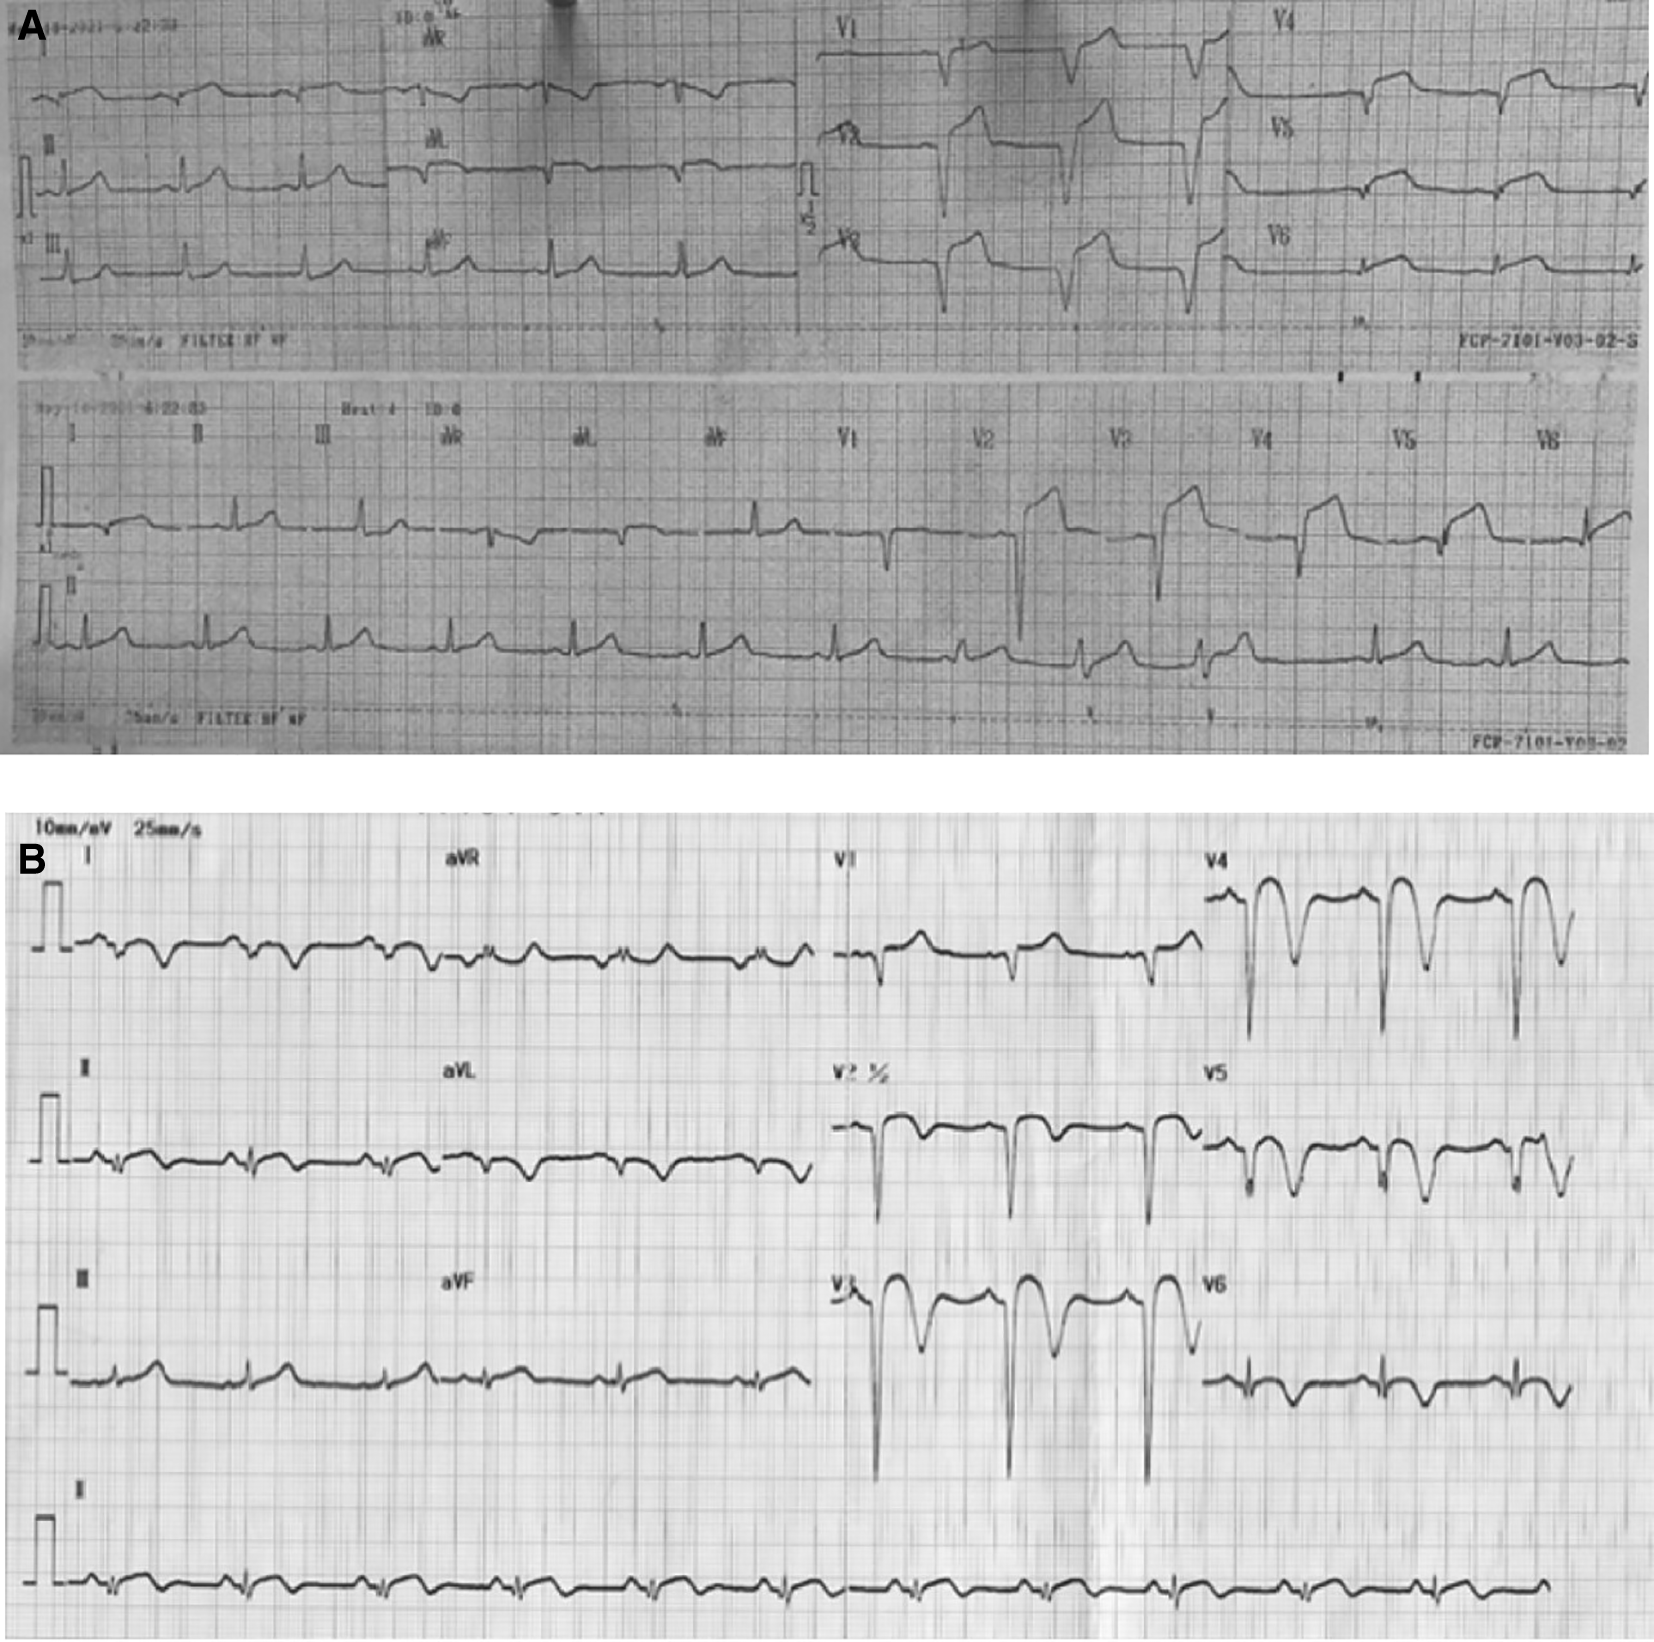

Physical examination revealed high blood pressure with normal heart rate and fever with temperature of 38°C. Chest auscultation showed crackles in both lungs without any rales or wheezing. ECG on 18 hours of chest pain onset showed ST elevation and pathological Q waves in V1-V6, I, and aVL (Figure 1A). Laboratory examination showed leukocytosis, high level of high-sensitive troponin T, hypoalbuminemia, proteinuria, and hyperlipidemia. Chest X-ray revealed infiltrate in both lungs. Echocardiography showed reduced left ventricular ejection fraction (LVEF) of 43%, hypokinetic at anterior and lateral segments, and left ventricle thrombus.

A. After 18 hours onset of chest pain, ST elevation and pathological Q waves were seen in V1-V6, I, and aVL. B. After percutaneous coronary intervention and medical therapy, no dynamic ST-T changes was seen in the ECG.

The patient received eptifibatide infusion, heparinization, oral dual antiplatelet with aspirin and ticagrelor, ACE inhibitor, statin, nitrate, and antibiotic. On the following day, there was no chest pain and ECG did not show any dynamic ST-T changes (Figure 1B). The patient was then received steroid therapy and discharged with stable condition. Four months later, without any signs and symptoms, he underwent CAG that showed normal coronary arteries without any apparent atherosclerotic lesions (Figure 2C).